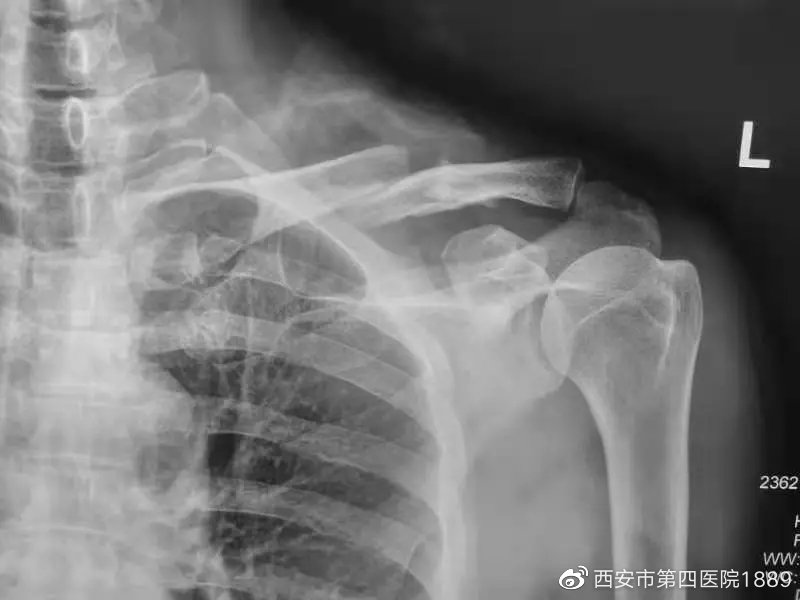

患者宋某,因摔倒致左侧肩关节疼痛伴活动障碍1天,去大差市院区就诊,姬海鹏副主任医师接诊,经过详细询问病史及体格检查后,考虑为左侧锁骨骨折,X线片结果证实了专家的诊断。与家属沟通并征得知情同意后,在医院领导及综合办的协助下,患者当天即入住航天城院区过渡病房。

术中X线片